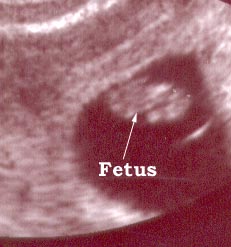

Photo Two

9 weeks fetus

This is a nine weeks pregnancy as seen using a vaginal probe.